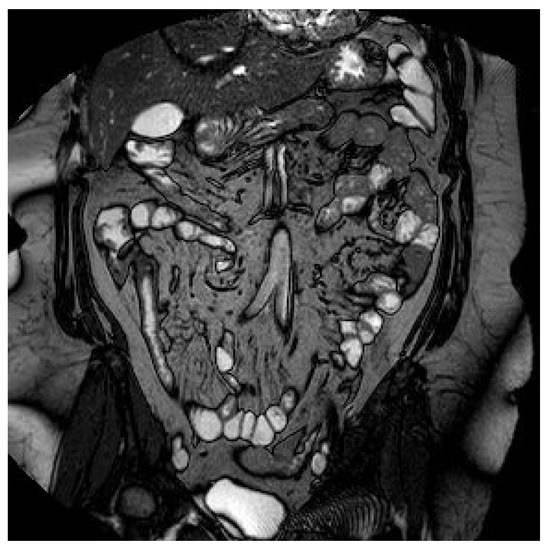

1.1. Case 1